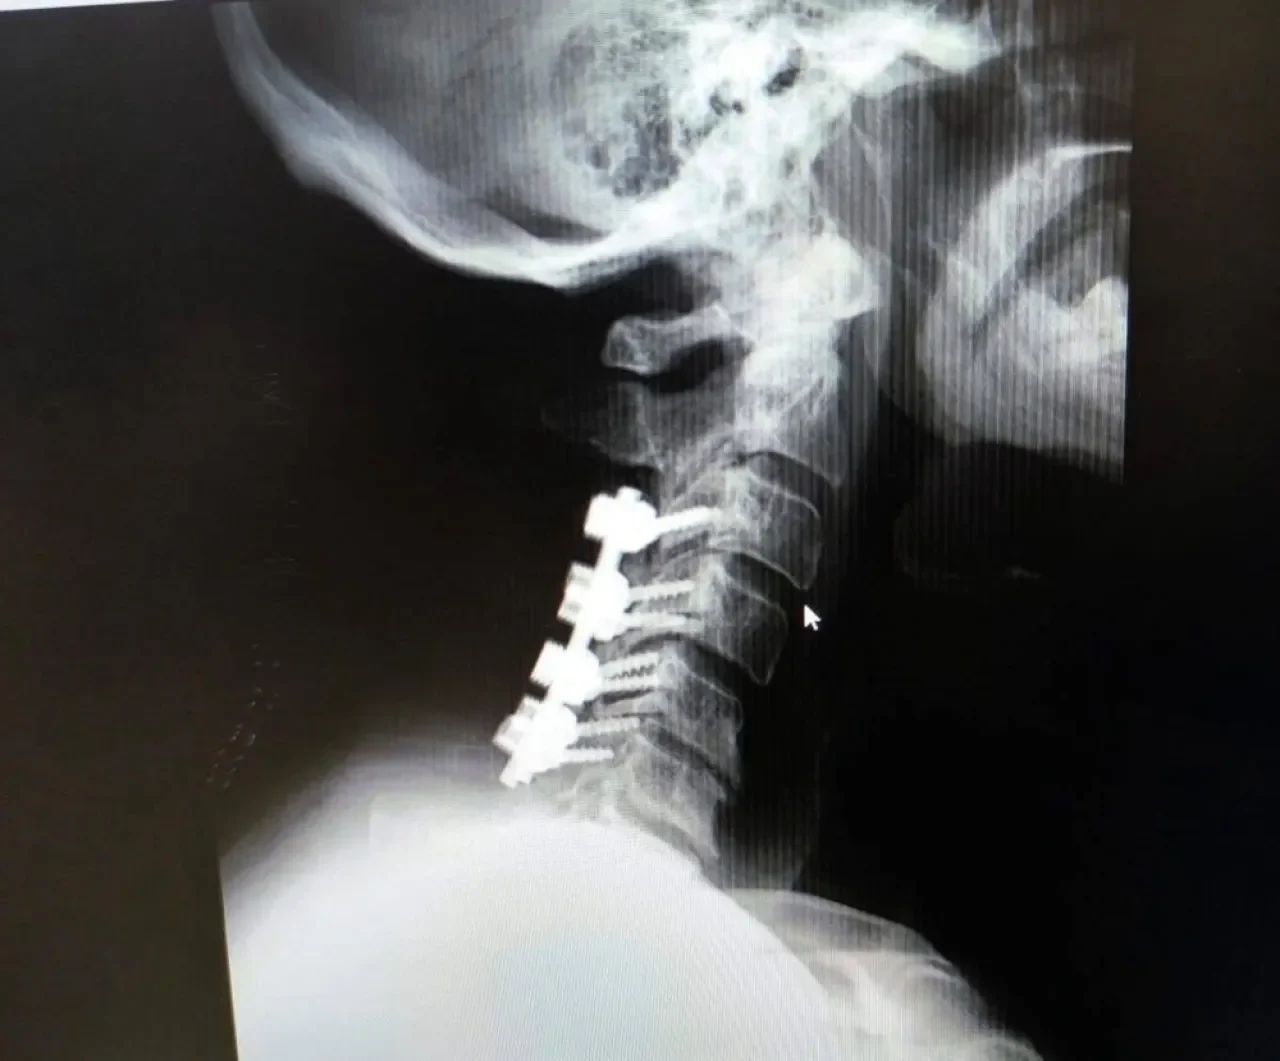

العموم نيوز: أجرى فريق طبي جراحي متخصص في قسم جراحة الدماغ والأعصاب في مستشفى الكرك الحكومي عمليتين جراحيتين تعتبران من العمليات النوعية التي يتم إجراؤها لأول مرة في المستشفى. حيث تم إجراء العملية الأولى باستخدام تقنية التداخل المحدود لإزالة انزلاق غضروفي ضاغط في الفقرات القطنية، بينما تمثلت العملية الجراحية الثانية في إزالة ورم من عظم الجمجمة.